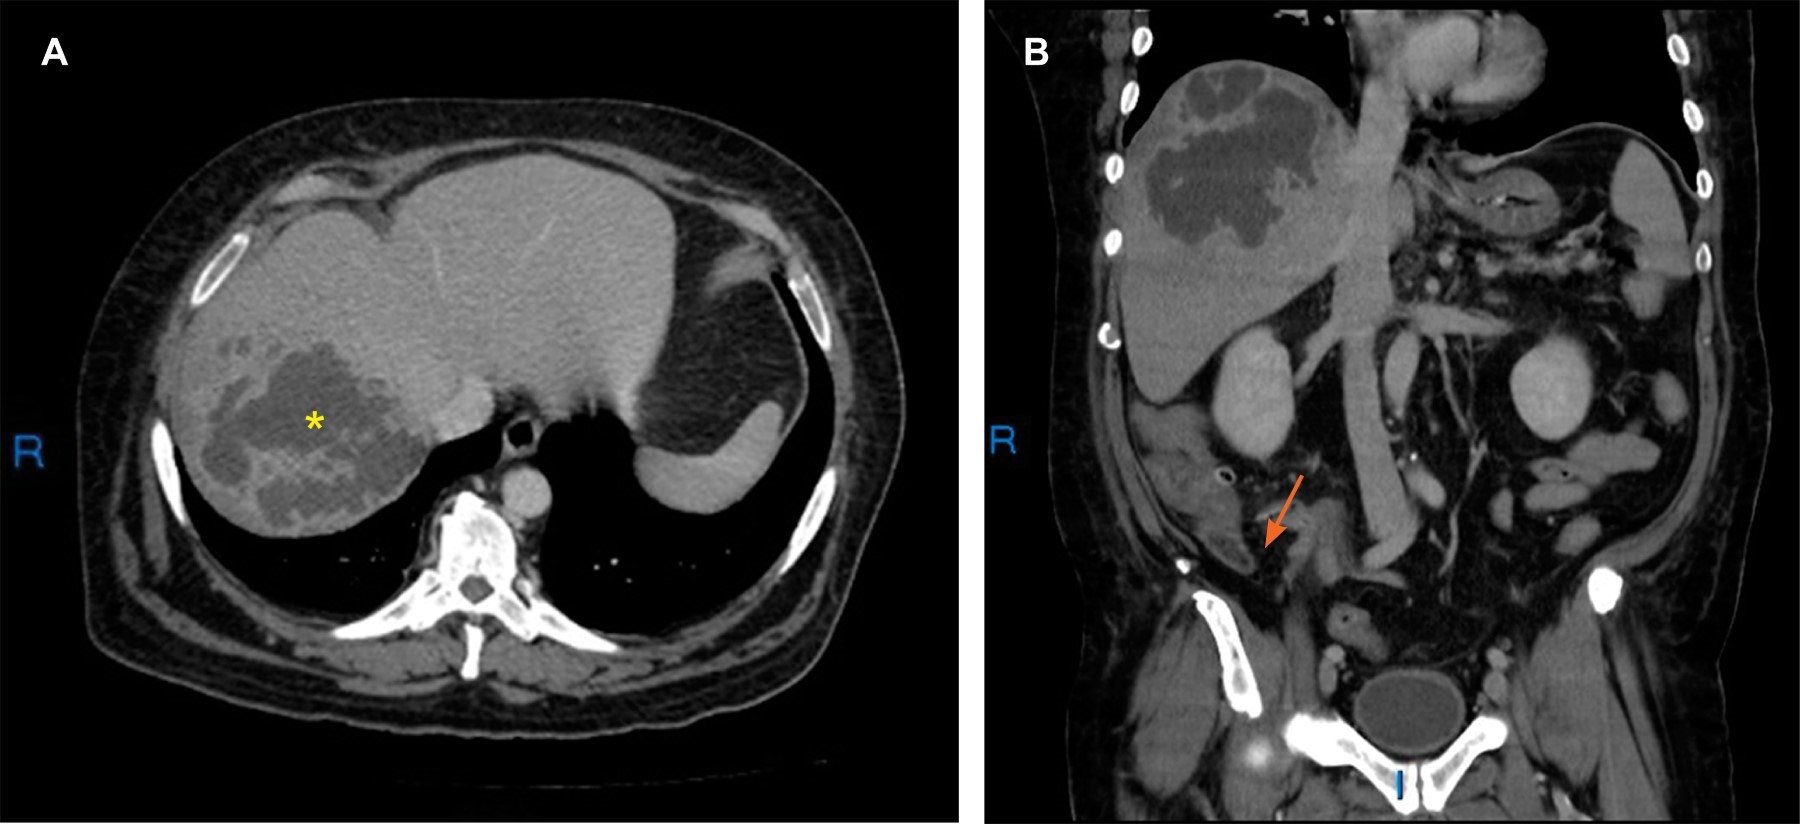

Se decide complementar con tomografía contrastada para mejor caracterización; se observa, en segmentos VII y VIII hepáticos, imágenes confluentes de bordes irregulares de predominio hipodenso en rango de atenuación de -4 UH que presentan realce periférico al paso del medio de contraste de hasta 60 UH en relación con absceso piógeno en fase subaguda (Figura 2A), como hallazgo se identifica remanente apendicular con longitud de 23 mm y un diámetro anteroposterior de 12 mm, con cambios inflamatorios a considerar en relación con apendicitis del muñón (Figura 2B).

Figura 2